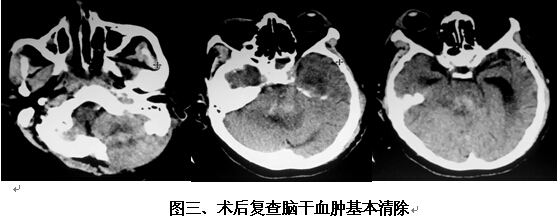

患者男,63歲,因突發(fā)神志不清2小時(shí)入院。入院時(shí)神志呈淺昏迷狀,頭顱CT提示腦干出血(橋腦、中腦區(qū)域,量約9ml)(見圖一)。神經(jīng)外科鐘三寶主任醫(yī)師查看患者后,分析患者病史、臨床表現(xiàn)及體查,結(jié)合影像學(xué)結(jié)果,考慮患者為重癥高血壓性腦干出血,需開顱行腦干血腫清除術(shù)。在發(fā)病后6小時(shí)左右,由鐘三寶主任醫(yī)師主刀,帶領(lǐng)李遠(yuǎn)志副主任醫(yī)師為患者進(jìn)行了手術(shù)。根據(jù)Brown兩點(diǎn)定位法則,采取枕下乙狀竇后入路,手術(shù)頭皮切口設(shè)計(jì)為勾型,骨窗大小約3cm*4cm(見圖二),術(shù)中清除腦干血腫約10ml,手術(shù)非常成功。術(shù)后復(fù)查頭顱CT提示腦干血腫基本清除(見圖三)。